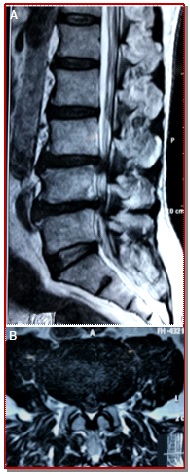

The aim of our study is to evaluate the clinical and functional outcome following lumbar laminoplasty with posterior element reconstruction with mini-plate and screws for multilevel lumbar canal stenosis. This study was done on 40 patients (18 males and 22 females) of degenerative multilevel lumber canal stenosis patients underwent open double door lumbar laminoplasty with posterior element reconstruction with mini-plate and screws from January 2015 to June 2018. Thirty four patients underwent surgery for 2 level involvement and 6 underwent for 3 level involvement of lumbar canal stenosis. The mean post-operative hospital stay was 5.2 ± 1.1 days. Per-operative complication was dural tear in 2 cases. Pre-operative mean VAS score of back pain and leg pain were 7.0 ± 0.7 and 7.2 ± 1.1 which were significantly reduced to 1.0 ± 0.2 and 1.0 ± 0.8 respectively at final follow-up. All patients were followed-up for minimum 1 year. Pre-operative mean Japanese Orthopedic Association score was 8.6 ± 2.2 which was significantly increased to 14.8 ± 0.4 after 12 months of surgery. Pre-operative mean Oswestry Disability Index was 34.4 ± 3.0 which was significantly reduced to 8.5 ± 2.2 after 12 months of surgery. The outcome of lumbar laminoplasty with posterior element reconstruction with mini-plate and screws for multilevel lumbar canal stenosis show good result and can be one of the good option for the treatment for multilevel lumbar canal stenosis.